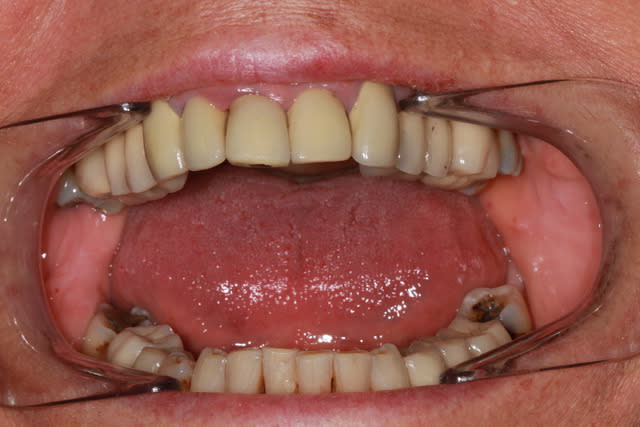

Pourquoi des facettes d'usures si importantes sur les 7? et bord libre 11?

Ttt fixe initial a modifié la DV ? hyper activité masseterine?

Inflammation paro chronique, sites actifs? qu'est ce qui bouge?

26,27,17,24 m'ont l'air foutues, 11 peut-etre aussi. Mobilites?

Ambivalence occlusale entre 17 16 et bloc ant. Sup trop serré .

Rien que de déverrouiller l avant , limer l angle proximal mesial de 17 et on en parle plus .

C'est sûre que quand on voit la différence qu'il y a au niveau du parodonte entre la maxillaire sup. et le maxillaire inf., l'usure de certaines dents, et la mauvaise adaptation de certaines couronnes, on est fortement incité à penser à une cause iatrogène...